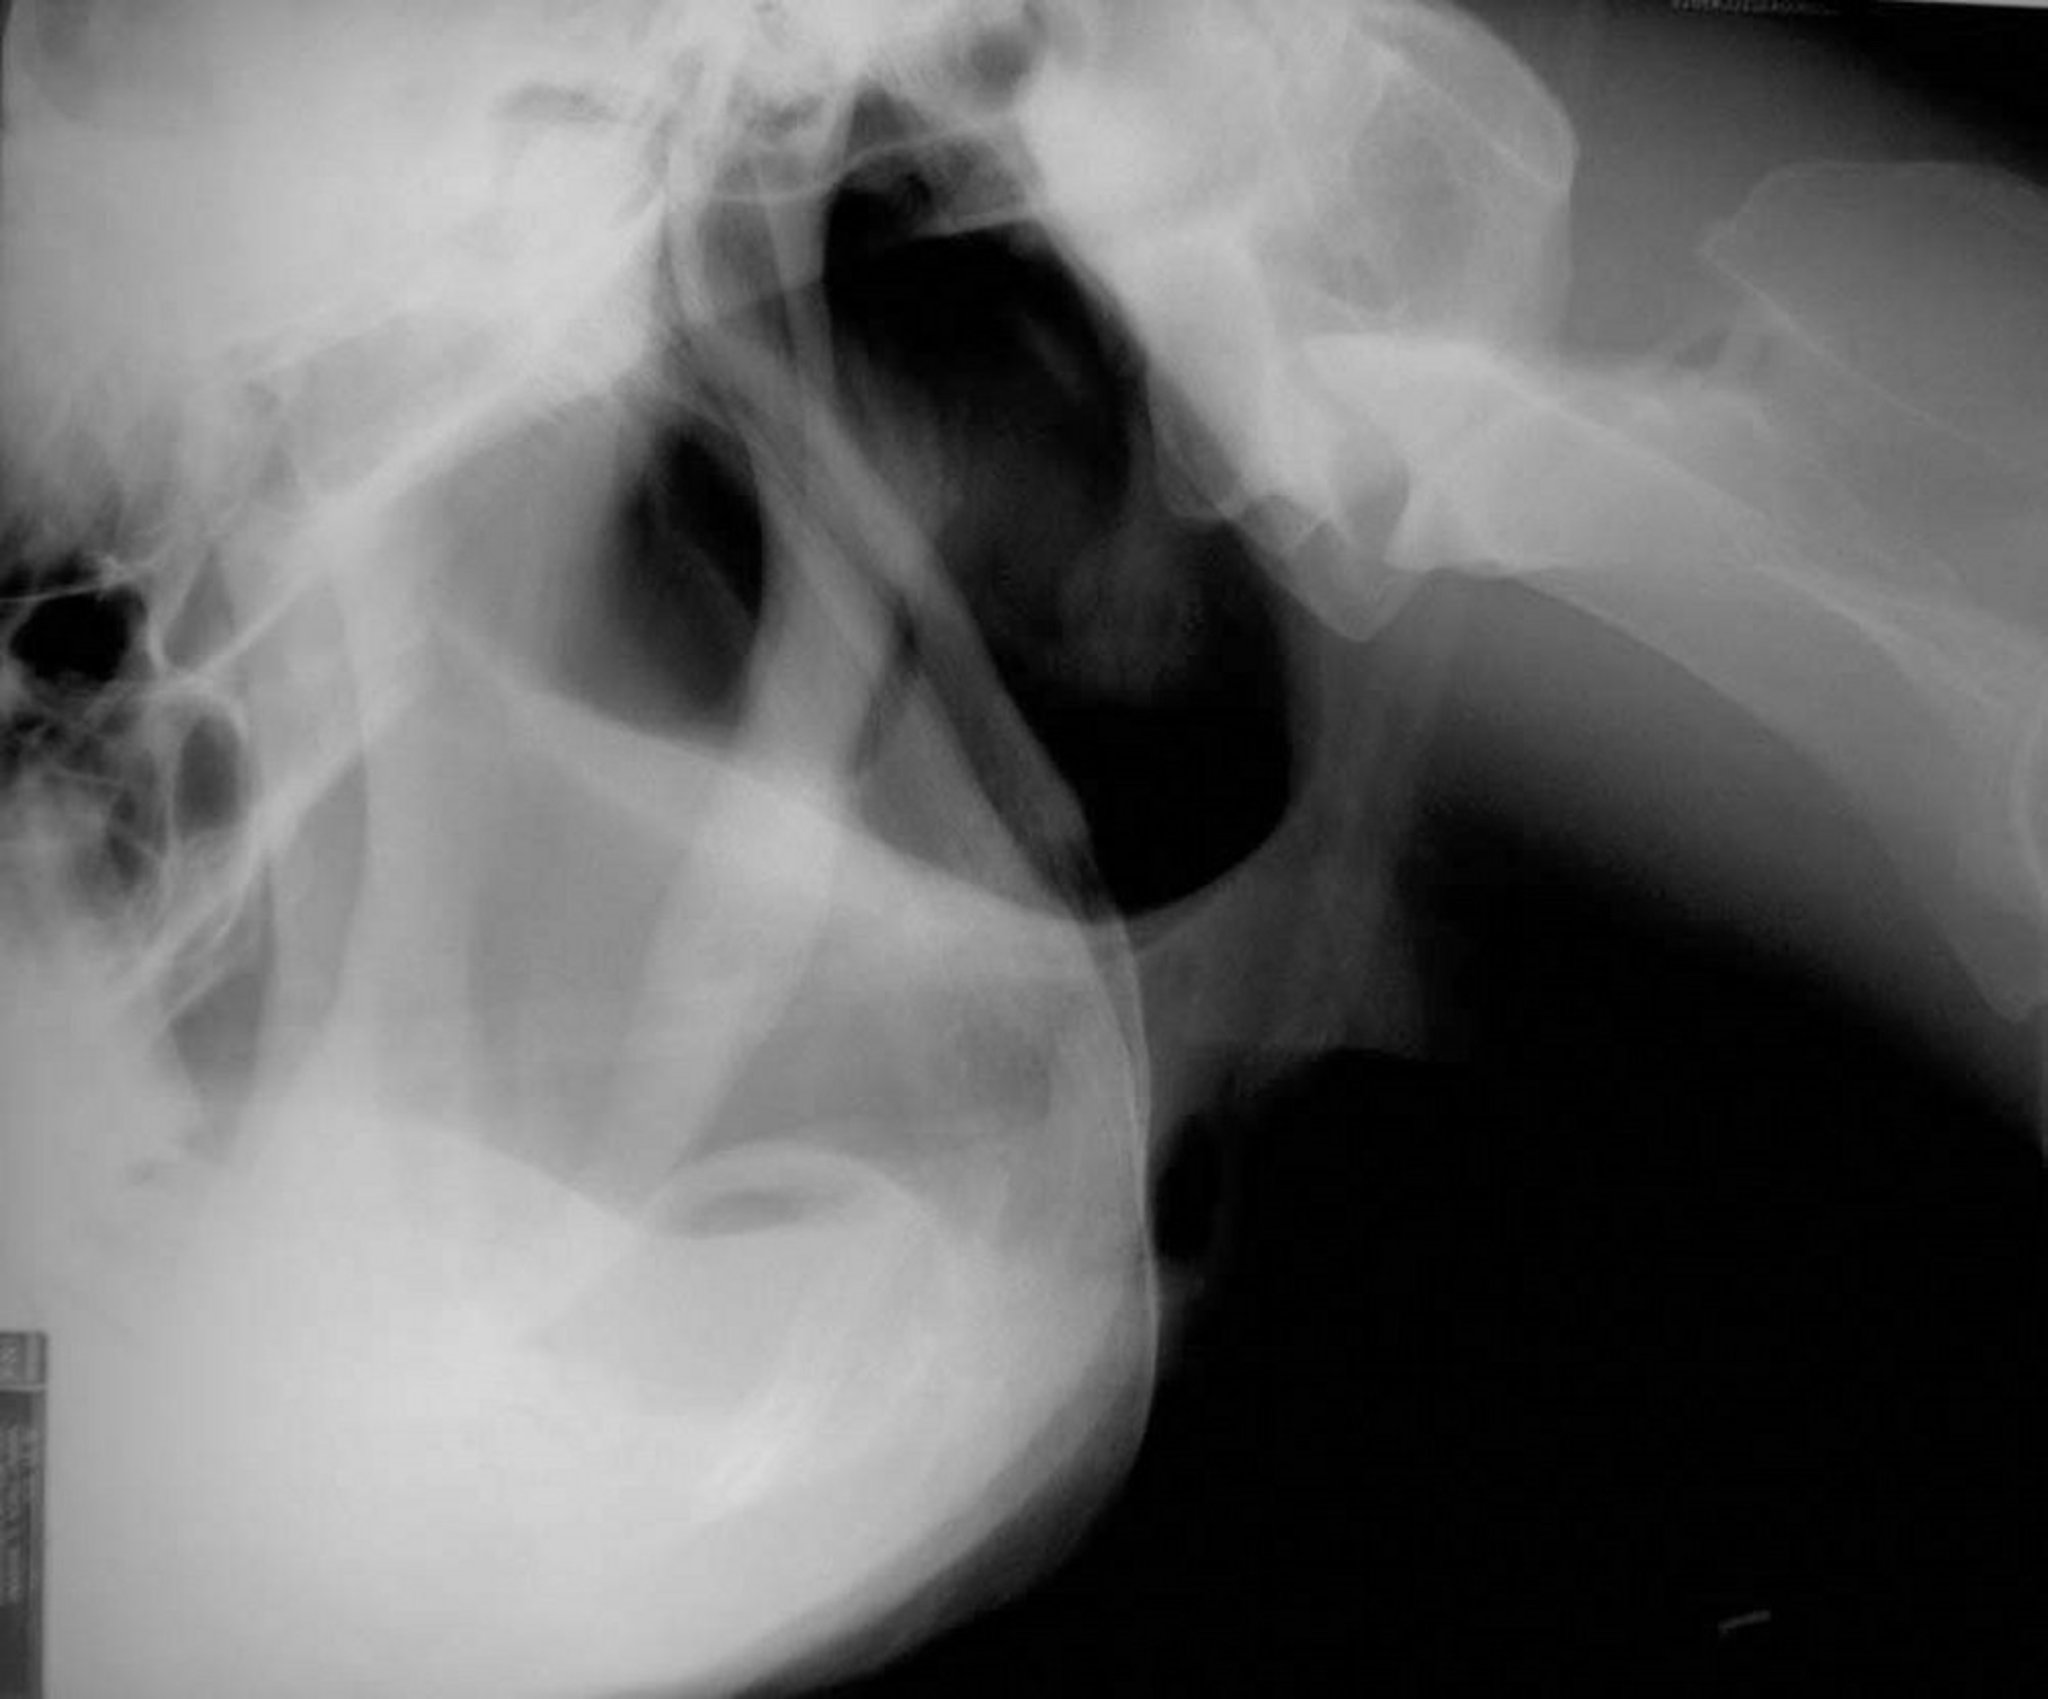

Fractura estilohioidea, caballo

Vista radiográfica lateral de una fractura estilohioidea en un caballo.

Cortesía del Dr. Sameeh M. Abutarbush.